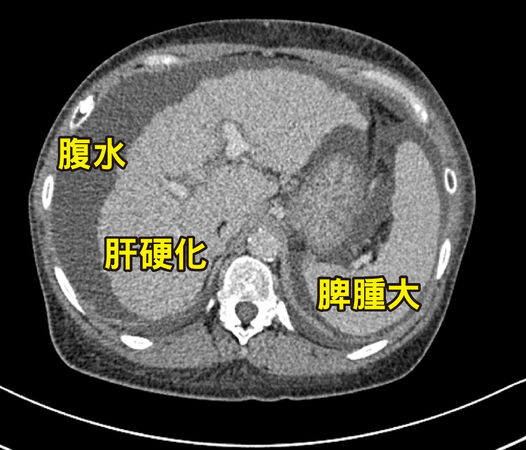

▲米德莉腹部電腦斷層掃描顯示肝臟已出現嚴重的「肝硬化」現象,並伴隨明顯的「腹水」蓄積以及「脾腫大」。

根據統計,因罹患PBC而需要肝臟移植者,約占全台肝臟移植個案的一至二成。林俊昌說明,以米德莉為例,病程已達重度肝硬化的C級,長期門脈高壓導致腹腔內側支循環異常發達且代償性擴張,加上肝功能衰竭引發的凝血因子合成障礙,使得術中極易發生大出血的高風險,致使移植手術更加困難,因此,在術前評估時,團隊嚴陣以待務必做好萬全的準備。